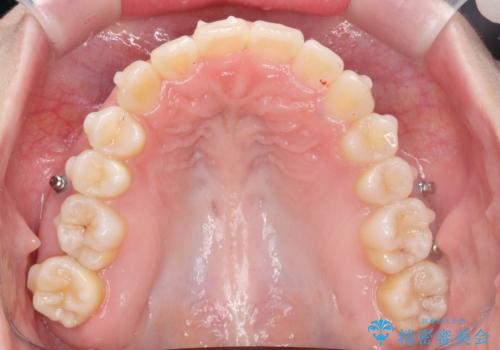

口腔内の清掃状態の良さに加えて、マウスピースを毎日きっちりと装着し、しっかりと使用していただけたことからワイヤー矯正は行わずにきれいに歯並びを治すことができました。

途中顎位が変わり、マイクロインプラントを併用した上顎臼歯の遠心移動が必要となったため治療が長期化しました。